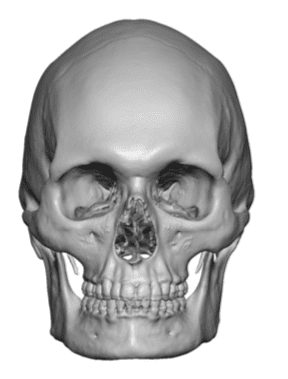

Desire for an improved head shape so that it looks rounder and not so peaked or sloped.

Placement of custom skull implant for parasagittal augmentation to create a rounder head shape. An example of what appears to be a high sagittal crest that is really low parasagittal skull areas.